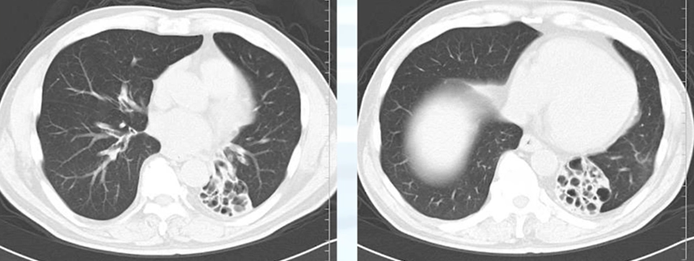

本レントゲンの特徴は、下降大動脈とシルエットサインが陽性で心臓裏に限局した嚢胞性病変が確認できるため気管支拡張症を疑います。

その場合は精査に進みます。CT所見です。

気管支拡張症がありました。その原因とすると抗酸菌・NTM・ABPA(アレルギー性肺アスペルギルス症)などが挙げられます。さらなる精査へ進むという順です。